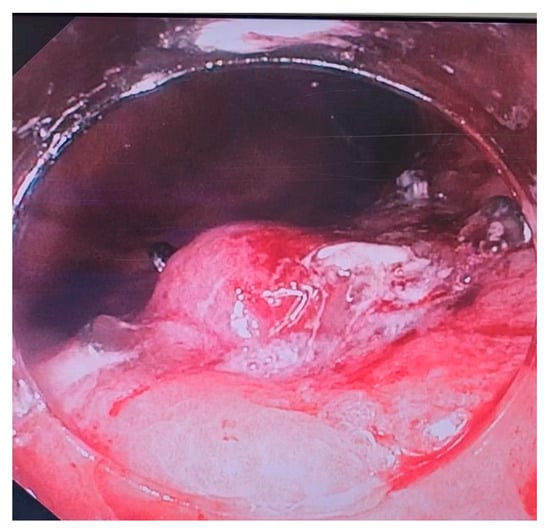

3. Endoscopic Suturing